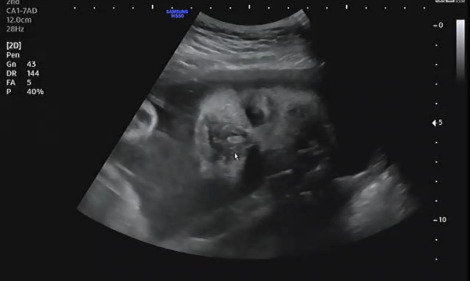

언제나처럼 진료시간에 맞춰 복부초음파로 태아의 상태를 확인했다. 시간이 지나감에 따라 내 품 안에 있던 아기는 초음파상으로 얼굴로 가득 차 보일만큼 성장하였다. 아이의 입이 꼬물거리며 움직이는 모습을 보며 설레는 마음으로 그동안 큰 이상은 없었는지 확인했다. 어느 때와 다름없이 햇님이는 자신이 건강하다는 것을 확인시켜주듯 양팔을 열심히 흔들며 엄마를 안정시켜줬다.